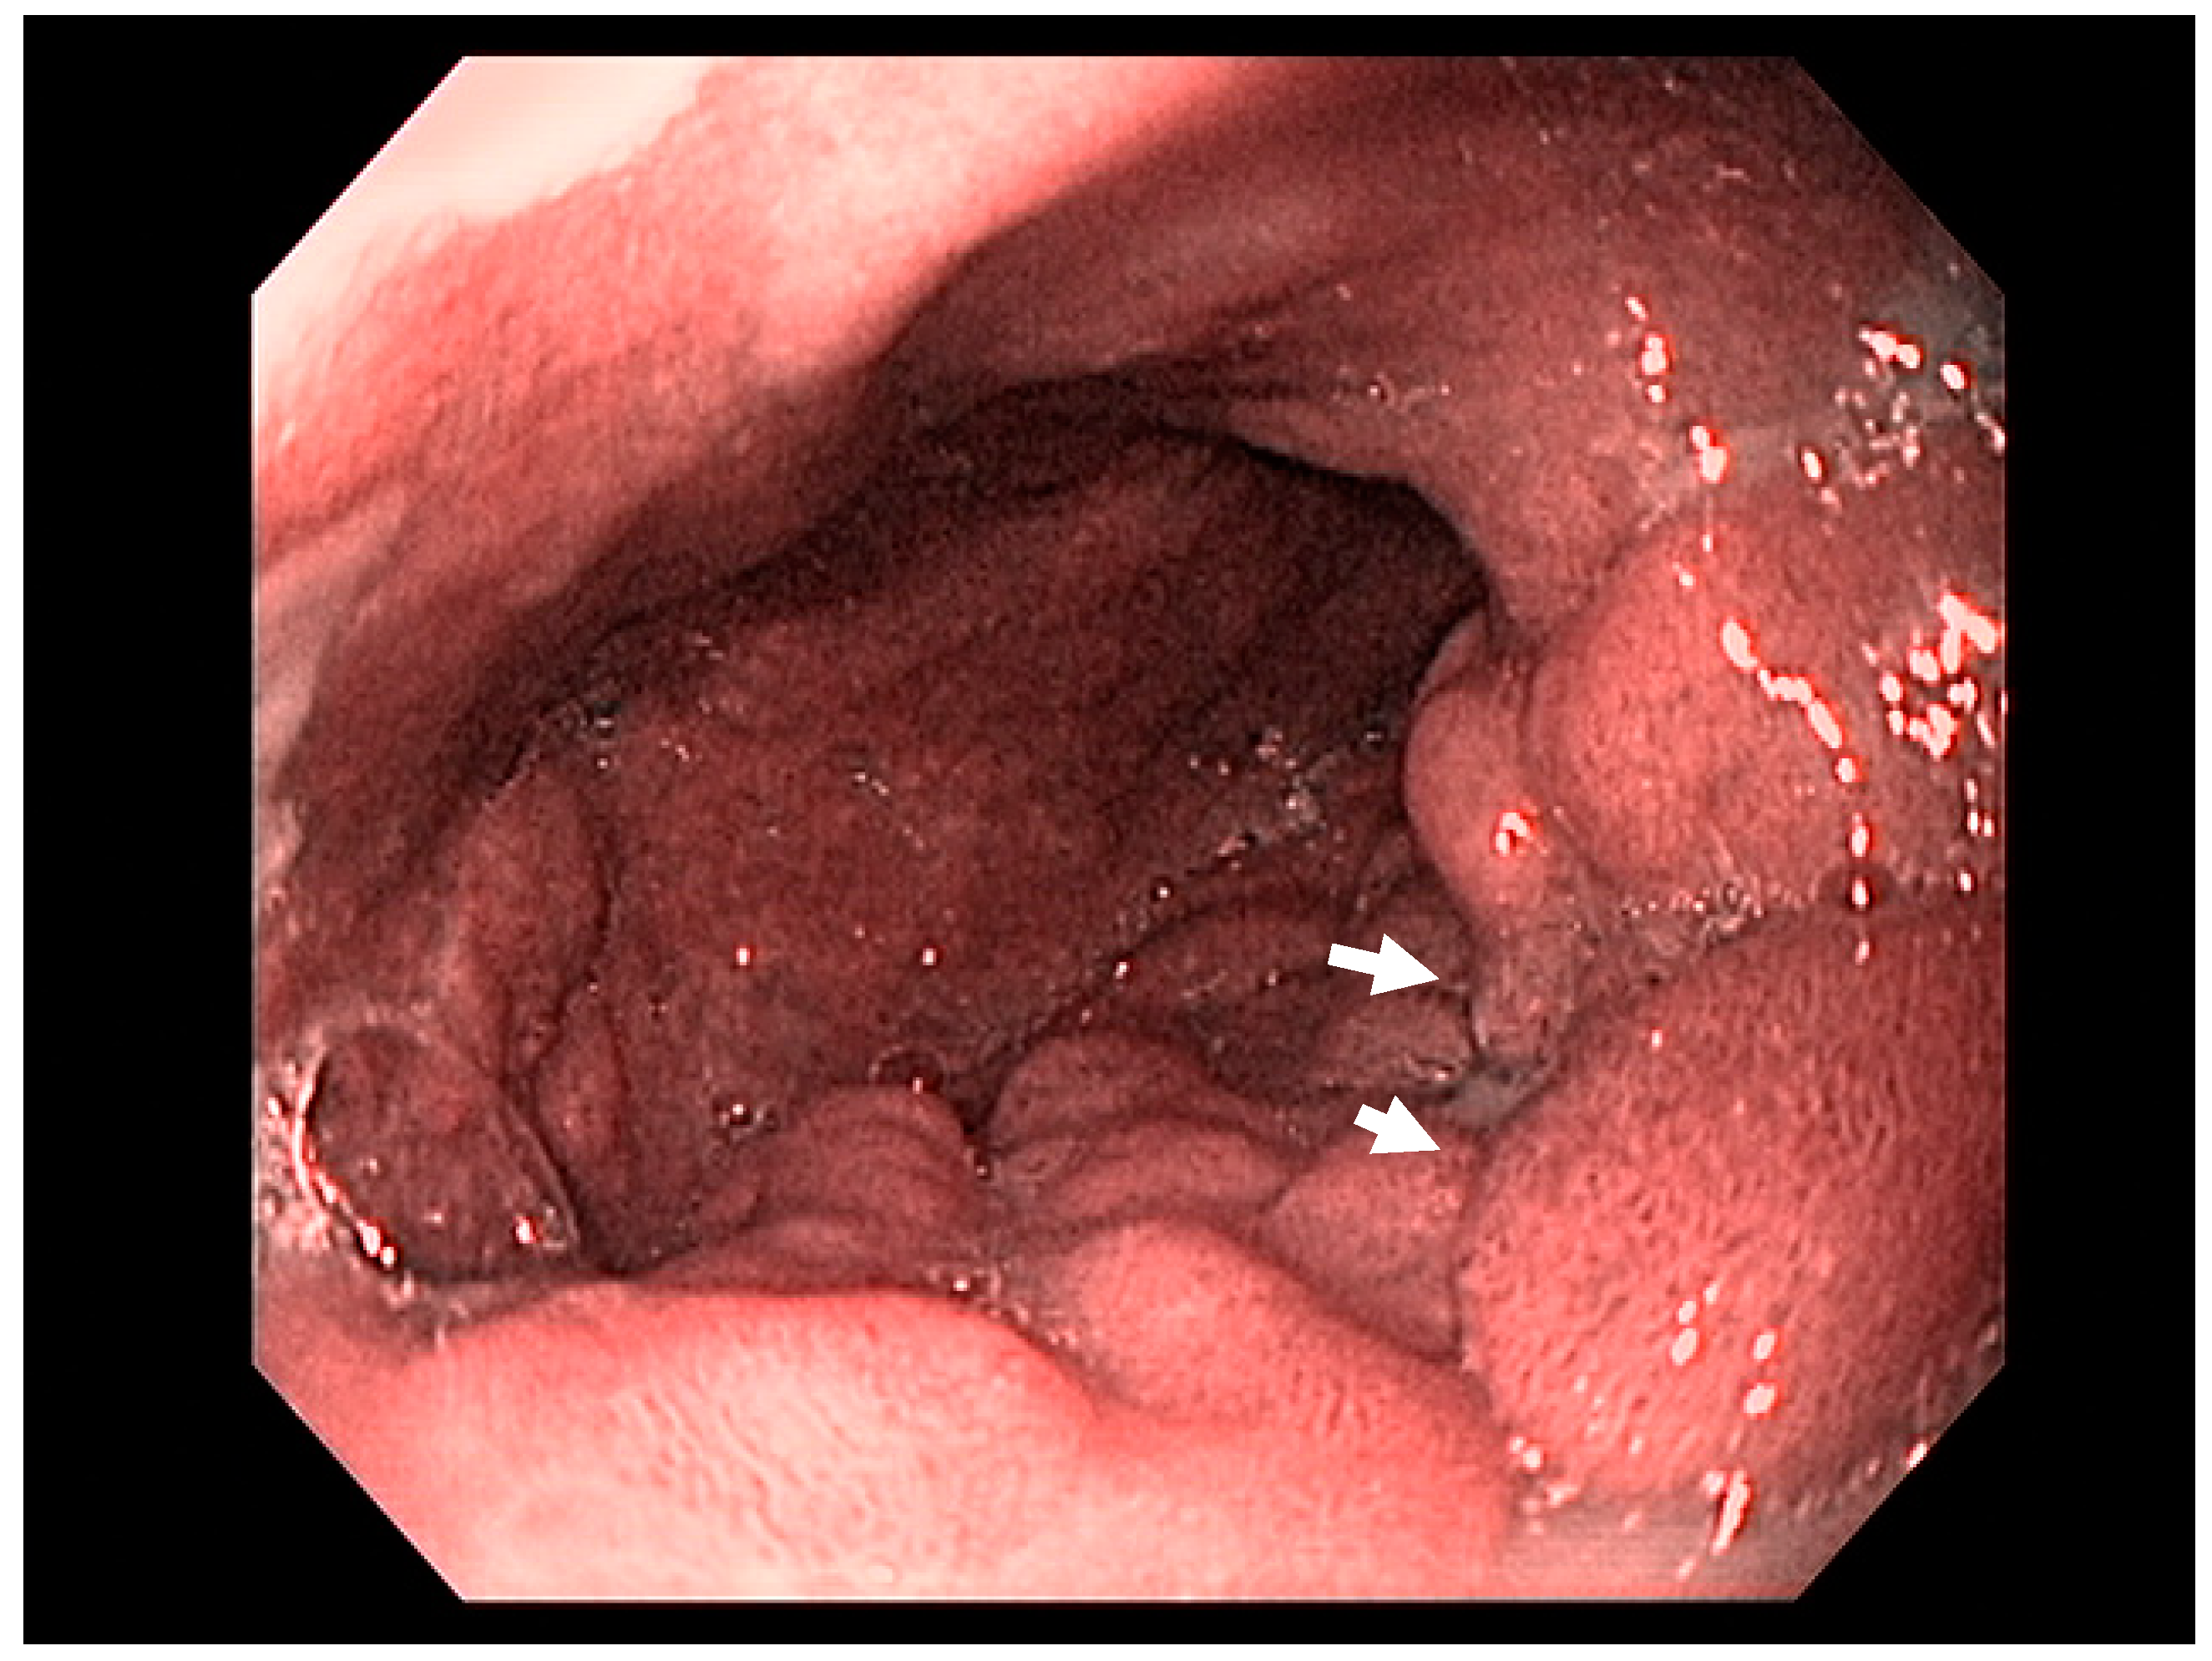

3.1. Endoscopic Therapeutic Options for Barrett’s Esophagus Associated Dysplasia

3.2. Endoscopic Resection Techniques for Early-Stage Esophageal Cancer (T1a and T1b)

4.2. Early Gastric Cancer (EGC)